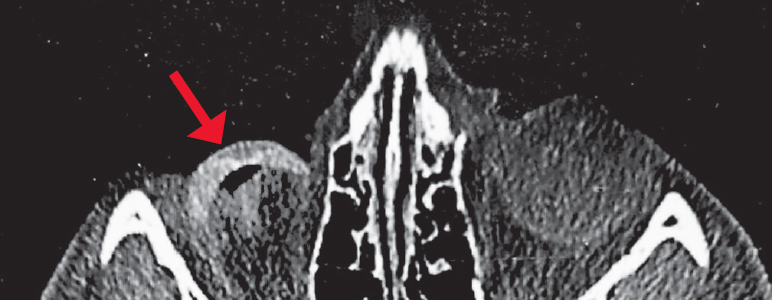

Fig. 8. MSCT of the orbit, axial section, bone reconstruction regimen. The state after enucleation of the right globe because of retinoblastoma without formation of a supporting-motor stump and installation of an endoprosthesis. In the anterior parts of the right orbit, an external cosmetic prosthesis is visualized with its prolapse into the orbital cavity, as well as the optic nerve stump and extraocular muscles

Рис. 8. МСКТ орбиты, аксиальный срез, режим костной реконструкции. Состояние после энуклеации правого глазного яблока по поводу ретинобластомы без формирования ОДК и установки эндопротеза. В передних отделах правой орбиты визуализируется наружный косметический протез с пролабированием его в полость орбиты (КТ-признаки энофтальма, стрелка), а также культя зрительного нерва и глазодвигательные мышцы